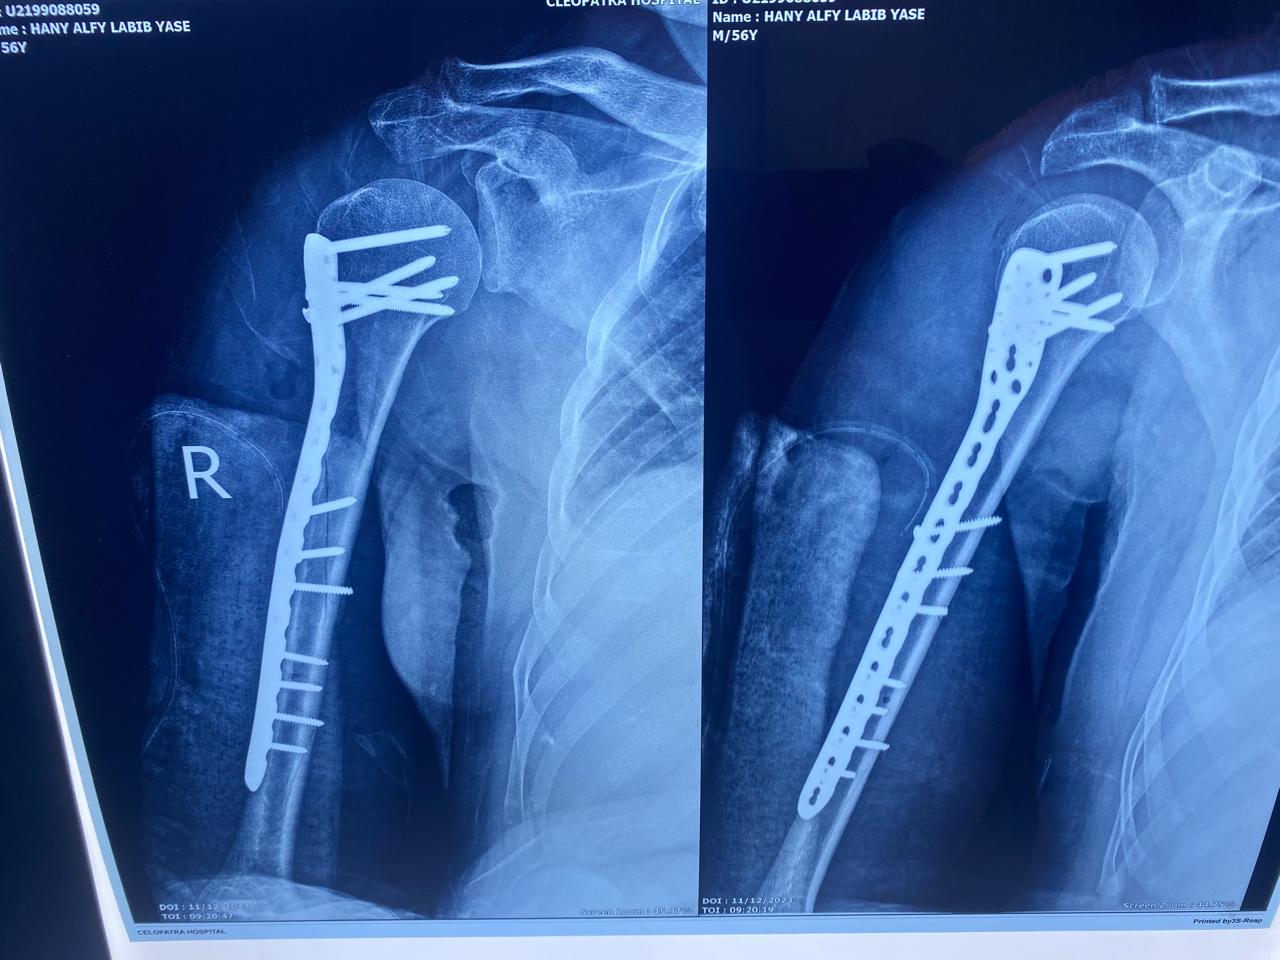

الاشعات بعد التثبيت تبين رجوع الكسر لطبيعته تمامًا.